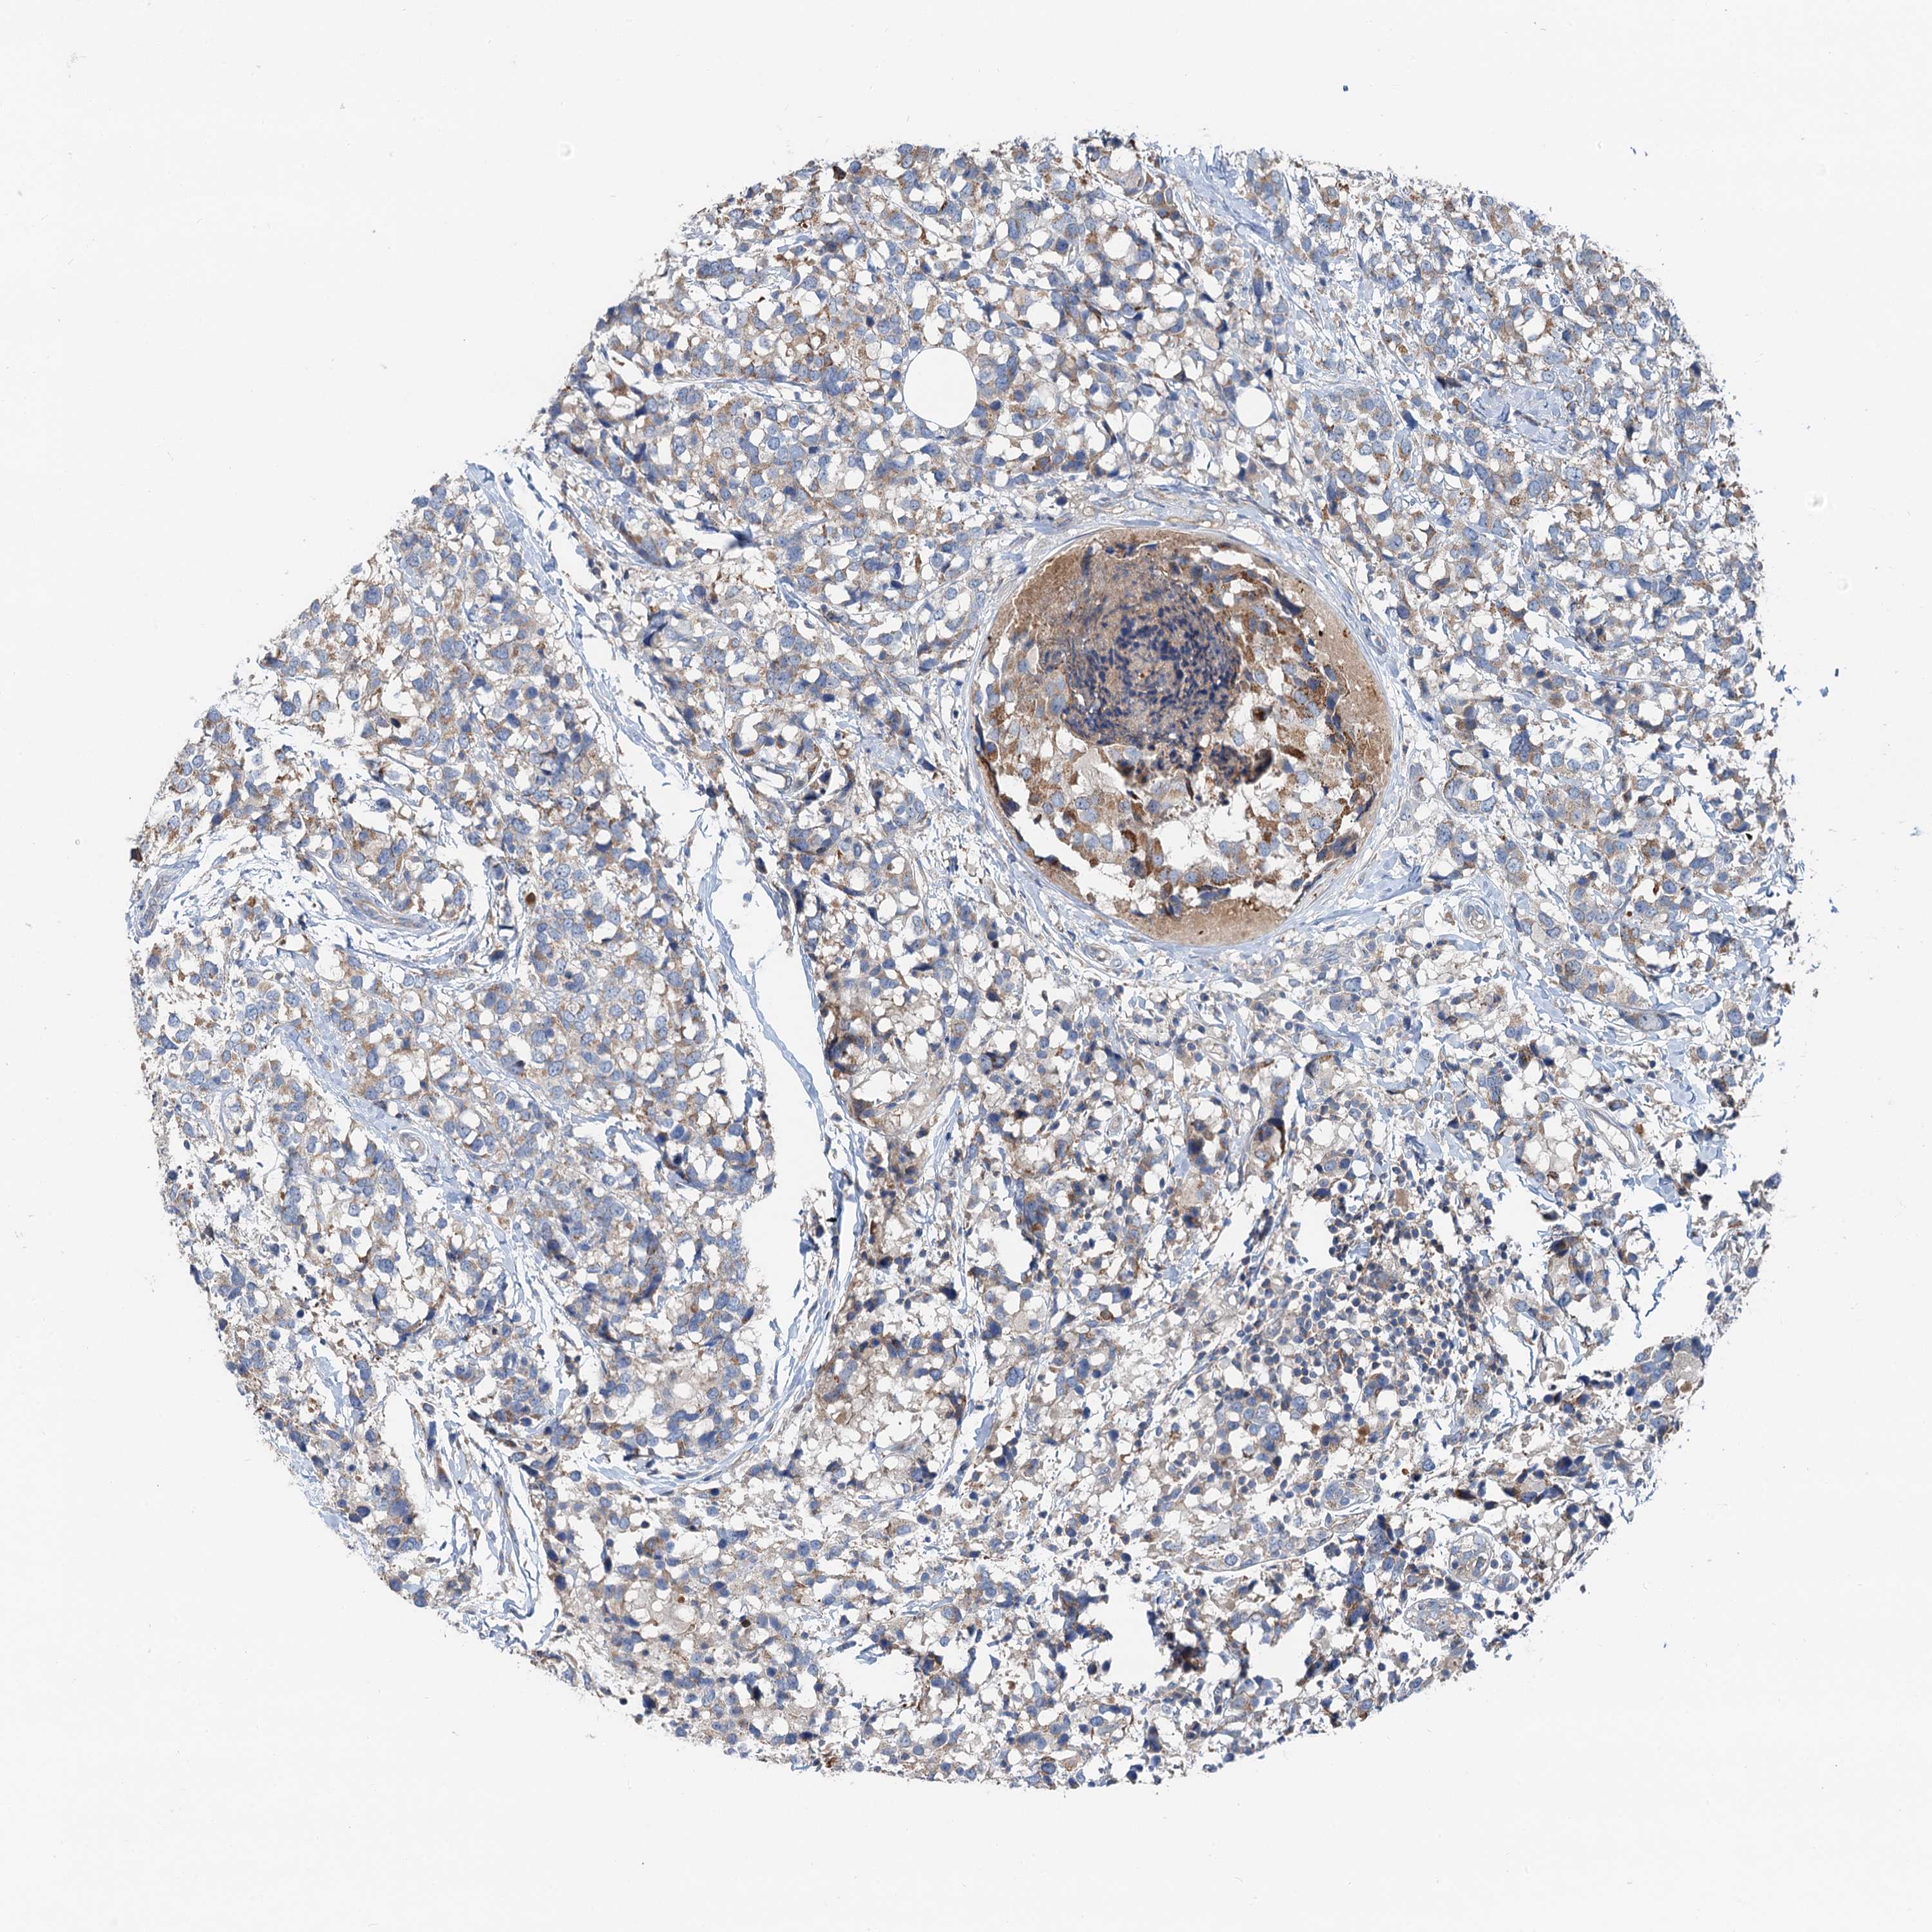

CANCER BREAST CANCER Show tissue menu

BRCA TCGA BRCA VALIDATION PROTEIN EXPRESSION